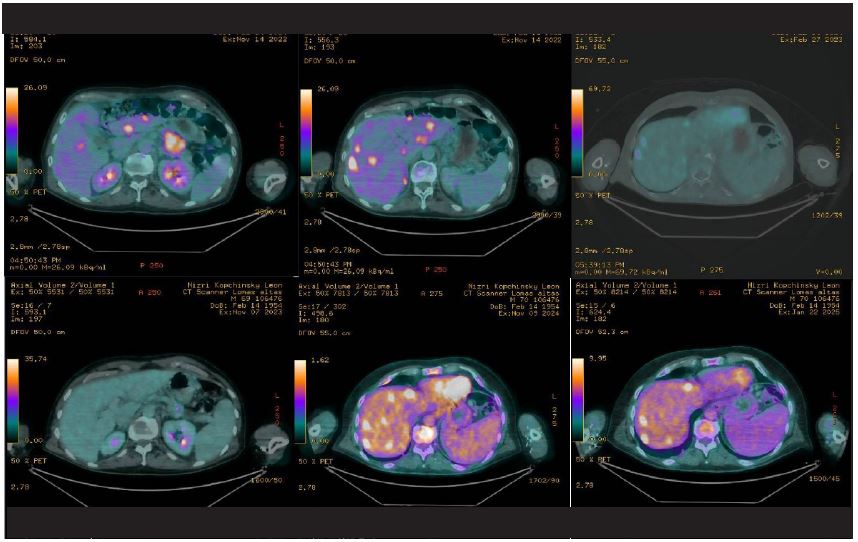

In november 2022 he underwent a new clinical evaluation, with a PET/CT with fluorodeoxyglucose as an imaging agent labeled by a radioactive isotope of fluorine-18 (18F-FDG total of 13.42 mCi) scan, which showed a solid heterogeneous lesion on the tail of the pancreas measuring 41 × 38 × 33 mm with a SUVmax of 7.19. The lesion encased the splenic artery over 180°, with thrombosis over the splanchnic vein. It was associated with para-aortic adenopathies and multiple hepatic intraparenchymal and hypovascular lesions, the largest measuring 17 mm in the segment III with an SUVmax of 19.13 (Figure 2a/b). On November 7th, 2022, he underwent a core needle biopsy of one of the metastatic lesions localized on the left hepatic lobule which revealed a pancreatic adenocarcinoma. On December 7th, 2022 the genomic profiling test Foundation One CDx was used to evaluate for BCRA1/2 mutations; the patient tested negative for BCRA1/2 but positive to ATM R35 loss, as well as KRAS G12V mutation, preserved MSI, and a TMB of 4 mut/Mb. Physical examination at the moment revealed no clinical signs, with a Karnofsky evaluation of 90% and an ECOG of 0.

Chemotherapy: The patient started systemic treatment on November 2022 with FOLFIRINOX (Irinotecan 150 mg/m2, Oxaliplatin 85 mg/m2, 5-Fluorouracil 400 mg bolus and infusion 2400 mg/m2 during 46 hours, adjusted 85% of total dosage) for 4 cycles, however the treatment was discontinued for 2 months due to a traumatic femoral fracture which was surgically resolved. Before the patient resumed treatment, he was evaluated with a new PET/CT scan with fluorodeoxyglucose (18F-FDG) on February 27, 2023 which exhibited a partial response according to Response Evaluation Criteria in Solid Tumor (RECIST) with a decrease of 58% in size of the main lesion in the tail of the pancreas, with a metabolic decrease of 29.5%. The liver was reported to show a decrease in the number of lesions (from 14 to 11) with a reduction of 50.9% of the aforementioned metabolism (Figure 2c).

The patient resumed treatment with the FOLFIRINOX chemotherapy regimen and completed 5 cycles from March 09, 2023 to May 18, 2023 for a total of 9 cycles. A PET/CT 18F-FDG scan conducted on May 2023, demonstrated stable disease according to RECIST compared to the previous study; however, the patient presented grade 3 neuropathy due to oxaliplatin on the 9th cycle of FOLFIRINOX, according to Common Terminology Criteria for Adverse Events (CTCAE) v4.0; whereby chemotherapy was adjusted, and oxaliplatin was discontinued. On June 20, 2023 the patient started treatment with FOLFIRI (Irinotecan 180 mg/m2, 5-Fluorouracil 400 mg bolus and infusion 2400 mg/m2 during 46 hours, adjusted 80% of total dosage) and was again evaluated for response with a PET/CT 18F-FDG scan after the 8th cycle of FOLFIRI which was administered on October 12, 2023.

On November 11, 2023 stable disease according to RECIST criteria was observed in the PET/CT 18F-FDG scan which allowed the patient to continue treatment (Figure 2d). There were no toxicities reported from the patient at each consult, and no clinical signs or symptoms of progressive disease recorded during each clinical examination. No other toxicities were associated with chemotherapy infusion and the patient underwent a total of 30 chemotherapy cycles with FOLFIRI until October 24, 2024. On November 12, 2024 a follow up PET/CT 18F-FDG scan showed progressive disease with increase in number, size and metabolism of the hepatic lesions, notably a metabolic increase of 263% in relation to hypodense lesion in liver segment IV measuring 12 mm, a preexisting lesion in liver segment II with a 133% increase in metabolism and an increase of 50% in size, and a third lesion on segment V, with a metabolic increase of 145% (Figure 2e).

With these new findings, the patient was programed for a new core needle liver biopsy over the right hepatic lobule, which pathology revealed a poorly differentiated pancreatic adenocarcinoma CK7 positive, CK20 positive, SMAD4 negative (loss of expression), Glipican negative (Figure 3). On December 5th, 2024, the patient started a third line of treatment with gemcitabine (1000 mg/m2) and nab-paclitaxel (125 mg/m2) every three weeks completing 3 cycles. The patient was evaluated in January 2025. On follow up his PET/CT 18F-FDG scan showed partial metabolic response of the pancreatic lesion with decrease of 30% in size, and a decrease of more than 30% of the metabolism previously reported in the hepatic lesions, although the size and number remained similar to the previous scan. (Figure 2f). Currently the patient has had an overall survival of 28 months, ongoing continuous treatment, is asymptomatic, dedicated to a full day regular work with a good overall quality of life.

Figure 2: Imaging pictures of patients before, during, and after treatment. (A & B) depicts the primary lesion with a PET/CT with fluorodeoxyglucose as an imaging agent labeled by a radioactive isotope of fluorine-18 (18F-FDG total of 13.42 mCi) scan shown a solid heterogeneous lession on the tail of the pancreas measuring 41×38×33 mm with a SUVmax of 7.19. The lession encases the splenic artery over 180°, with thrombosis over the splacnic vein. It is associated to a para-aortic adenopathy and multiple hepatic intraparenchomatous and hypovascular lessions (at least 14, the biggest measuring 17 mm at the segment III and SUVmax 19.13) associated with metastasic disease. (C & D) shows the response to initial treatment, and during maintenance with stable disease. (E) depicts progressive disease after treatment with increase in number, size and metabolism of the hepatic lesions, which reported: On segment 4, an increase in metabolism out of 263% over a new hypodense lesion measuring 12 mm; on segment 2, a preexisting lesion with an increase in metabolism of 133% and increase of 50% in size. × shows the follow up scan after second line treatment with change in chemotherapy, with response over metabolism measured in SUV max.